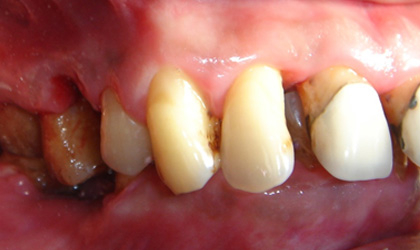

牙周組織破壞包括 :

骨頭吸收、牙齦發炎、牙齒動搖

牙周病有什麼症狀 :

1. 刷牙時或不自覺的牙齦出血

2. 牙齦顏色由粉紅色變為暗紅色

3. 牙齦紅腫、疼痛甚至化膿

4. 牙齒酸軟無力;對冷熱食物敏感

5. 牙齦萎縮,齒牙慢慢移位,齒間出現間隙

6. 牙齒鬆動